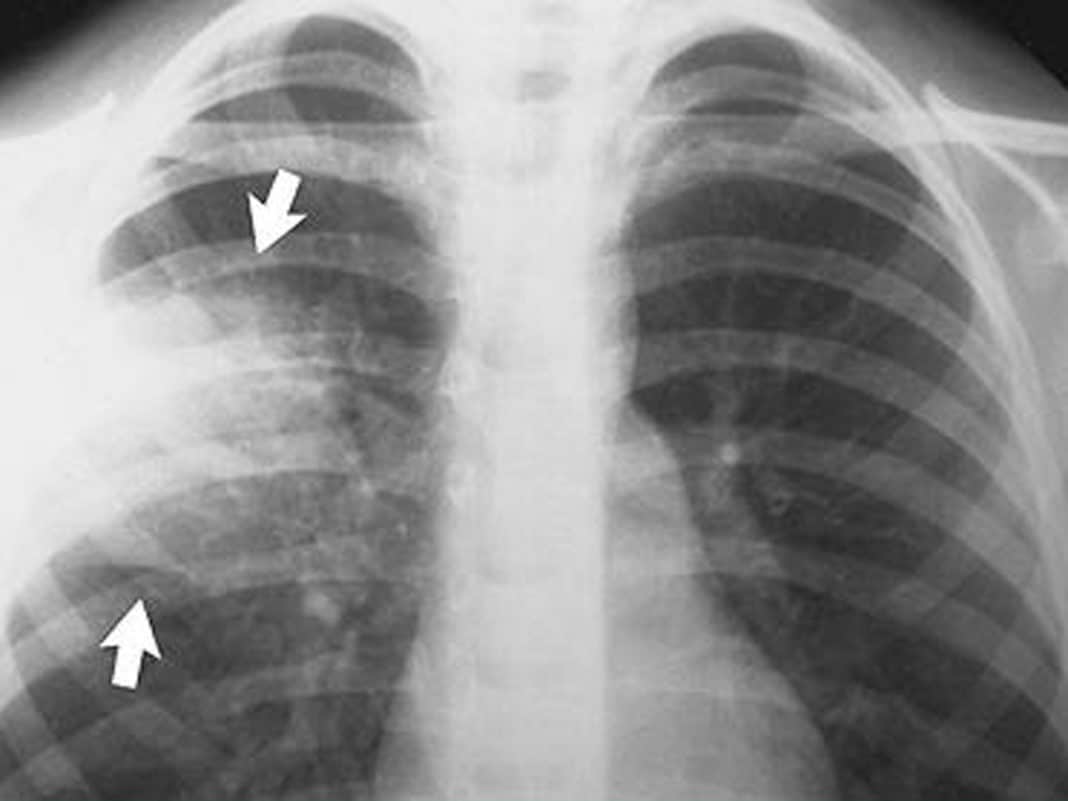

Снимок легких при туберкулезе является важным методом диагностики этого заболевания. На рентгеновских снимках можно увидеть изменения в легких, которые свойственны туберкулезу.

Очаговый туберкулез рентген

Очаговый туберкулёз ренген

Фиброзно очаговый туберкулез рентген

Фиброзно-очаговый туберкулез рентгенограмма

Фотографии снимков легких при туберкулезе

В данной статье представлены многочисленные фотографии снимков легких при туберкулезе, чтобы помочь вам понять, как выглядят изменения легких на рентгеновских снимках при этом заболевании.